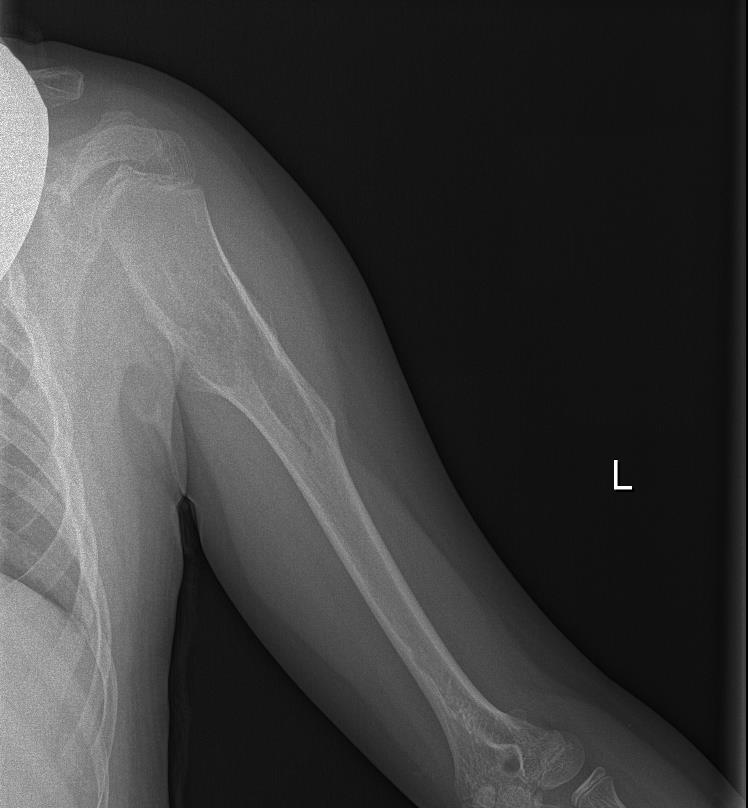

Radiografía de Miembro superior izquierdo: Se visualiza lesión lítica metafiso-diafisaria en húmero izquierdo expansiva con excrecencias óseas y margen estrecho con hueso sano.

Tras visualizar alteración en la ecografía del centro de salud, se deriva a radiología para realizar ecografía reglada y completar estudio con radiografía, así como realizar derivación para valoración por parte de Traumatología del Hospital Santa Lucía.